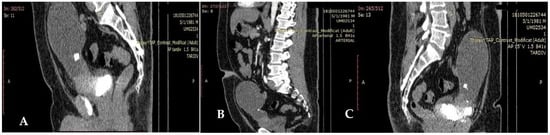

A contrast computerized tomography (CT) scan of the chest, abdomen and pelvis revealed parietal thickening of the antero-superior bladder wall (40 mm), with enhanced contrast. A heterogeneous, hypodense mass was located on the topography of the communication with a voluminous anterior bladder diverticulum (9 cm). The tumor had developed partly in the bladder, partly in the diverticulum and infiltration of surrounding tissue of the bladder near to the tumoral mass was identified.

No abnormal enhancement was identified. Small calcifications were seen in the lower part of the cystic mass. There was no retroperitoneal lymphadenopathy, ascites, or intestinal mechanical obstruction (Figure 1A–C).

Figure 1.

(A–C) Heterogeneous, hypodense mass develop partly in the bladder (A,B); infiltration of the surrounding tissue (C).